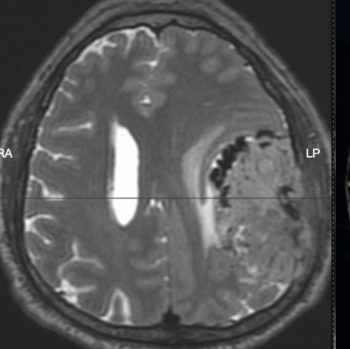

• Tumores cerebrales

• Hematomas (coágulos) Intracraneales: Epidurales y subdurales

• Alteraciones vasculares cerebrales

• Evento vascular cerebral (hemorragias)